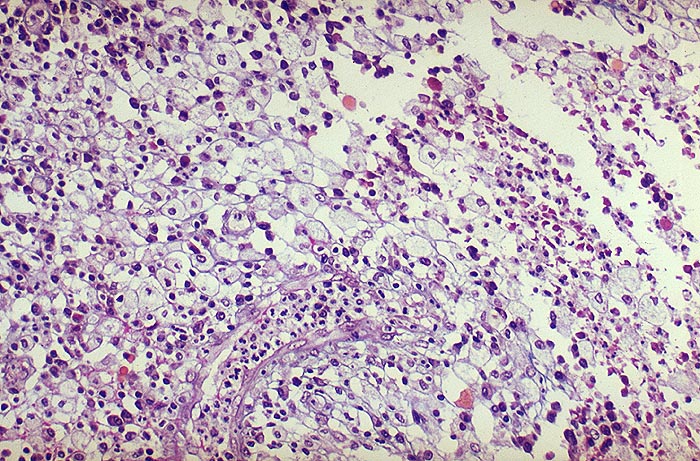

Xanthogranulomatöse Pyelonephritis

Typische Schaumzellen (Xanthomzellen) aus dem Granulationsgewebewall. Zwischen den Schaumzellen auch Lymphozyten-Plasmazellen sowie gelapptkernige Leukozyten.

Stets einseitige Pyelonephritis mit typischer Trias:

1. Obstruktion der ableitenden Harnwege zumeist durch Phosphatsteine

2. Coli oder Proteusinfekt

3. Störung der Leukozytenfunktion. Kommen tuberkuloide Granulome vor, wird fälschlicherweise oft eine Tuberkulose diagnostiziert. Bei Tuberkulose aber nie Schaumzellen. Die Malakoplakie der Niere ist im Gegensatz zur xanthogranulomatösen Pyelonephritis stets beidseitig.